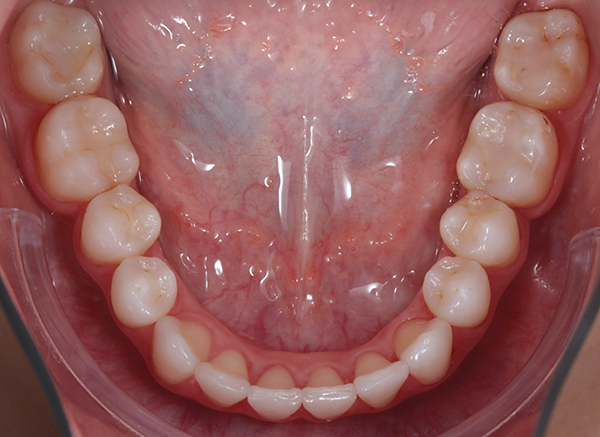

Fig 5. Preoperative intraoral occlusal views of the maxillary (Fig 4) and mandibular (Fig 5) arches.

Figure 5

Intraoral evaluation showed compromised oral health with generalized gingivitis and plaque accumulation (Figure 2). Many teeth had already been restored, and several restorations were failing. The maxillary dental midline coincided with the facial midline with a minor inclination. The lower midline deviated approximately 3 mm to the left side in reference to the upper midline. There was moderate crowding in the maxilla, mainly on the right side, and severe crowding in the mandible. Canines on the right were in Angle class III malocclusion, while molars and canines on the left were in mild class II malocclusion. Radiographic evaluation revealed crowding, missing teeth, and failing restorative as well as endodontic treatment (Figure 3).

The interdisciplinary treatment plan to establish good oral health, esthetics, and function included prophylaxis and oral hygiene instructions as first steps. Respective teeth were extracted and orthodontic treatment was carried out. Figure 4 and Figure 5 depict the intraoral situation before orthodontic treatment with fixed appliances and ceramic brackets; Figure 6 through Figure 8 show the situation after orthodontic treatment, which lasted 18 months.